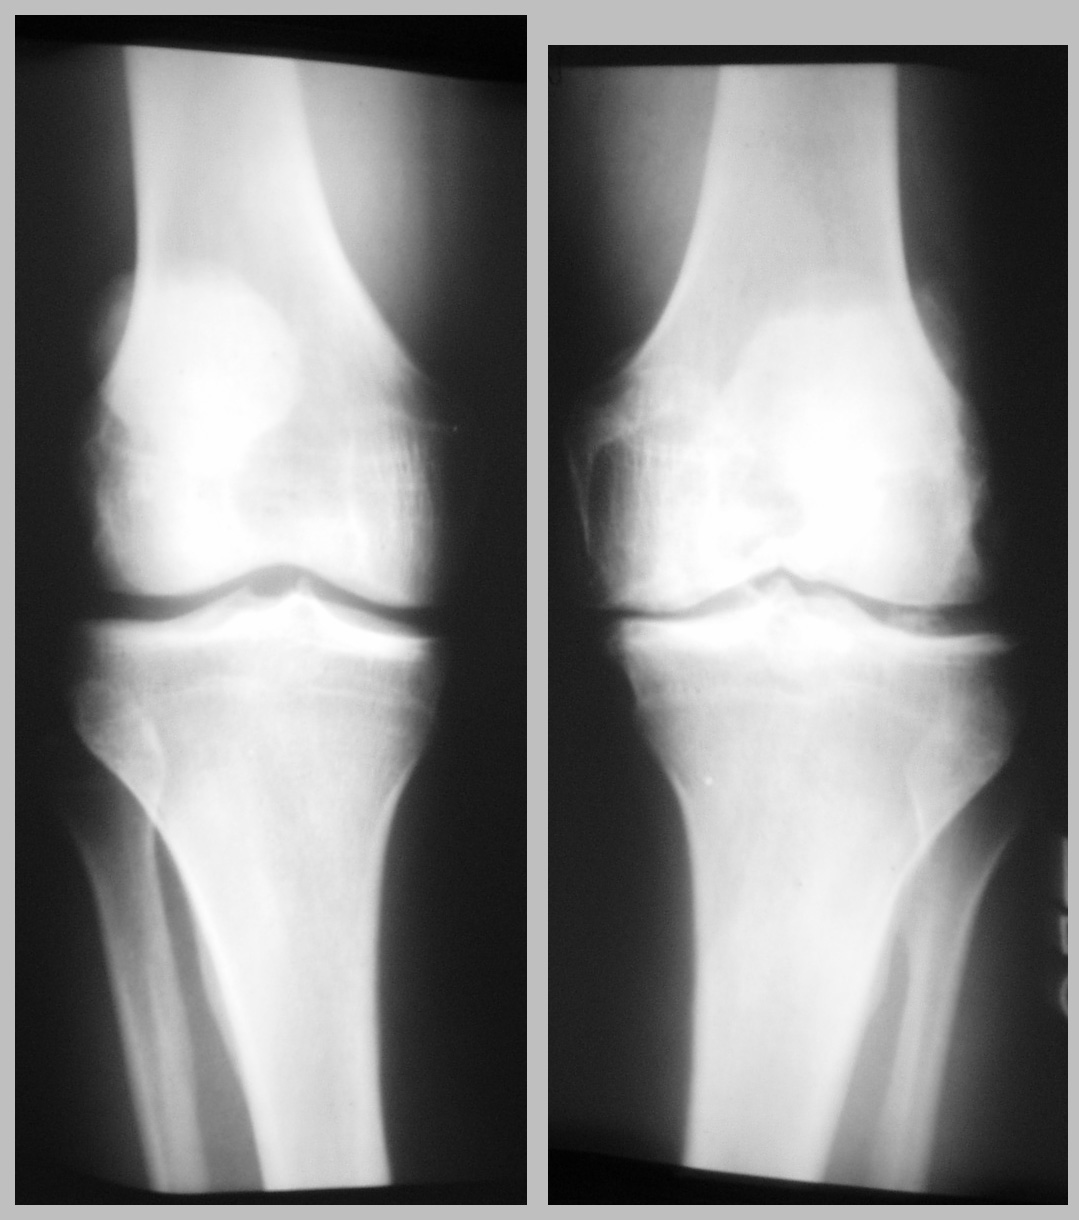

This hurts.   Trust me.

Scroll around and feel my pain.

OK, that's enough, go back to the Knee Saga.